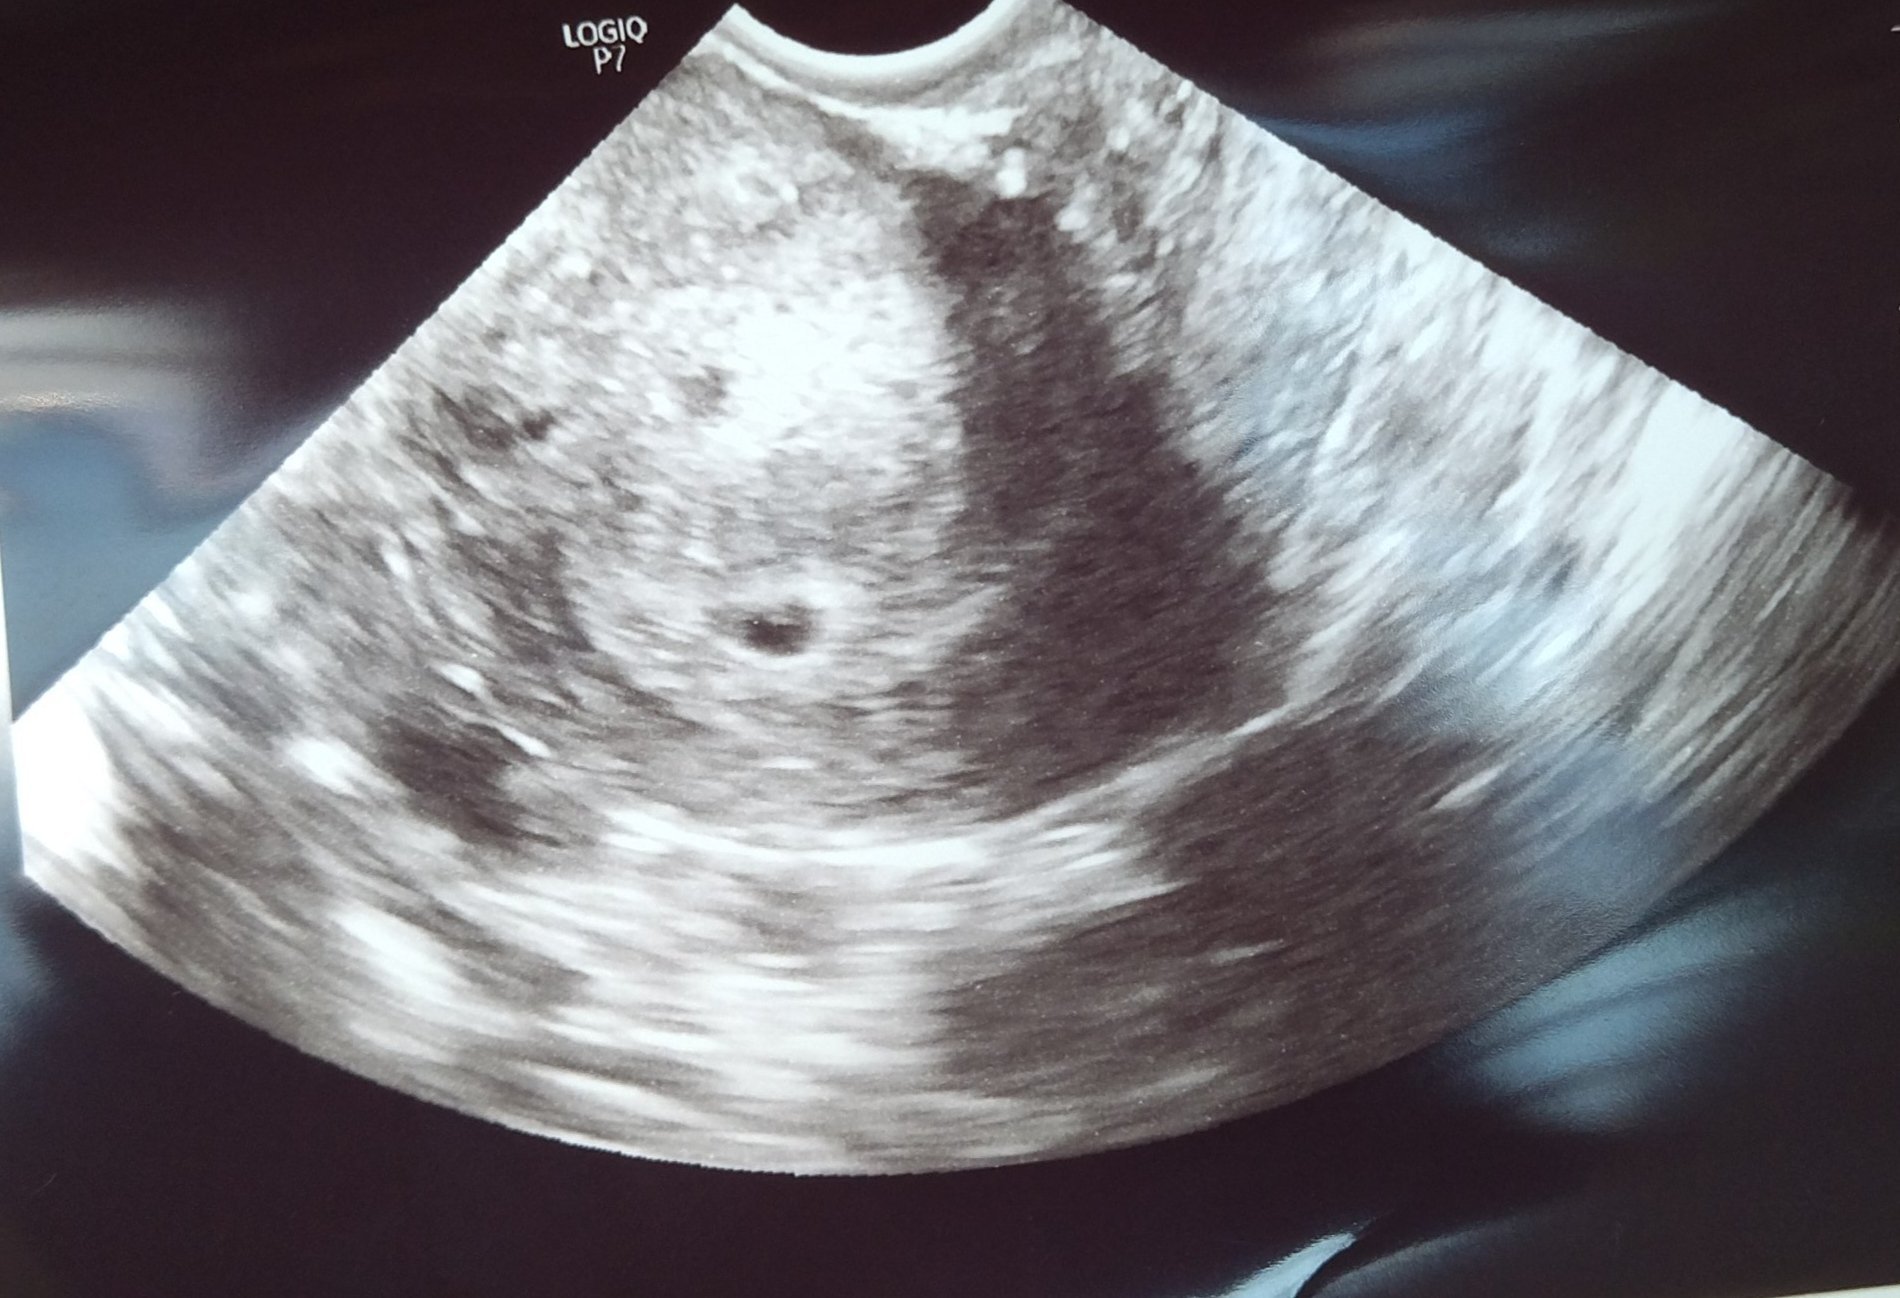

• Мнения: 447

Добавям снимката от ехографа, изглежда ми доста некачествена. Чудя се дали междувременно да потърся второ мнение с по-добра апаратура, не знам дали има смисъл да насилвам нещата или просто да се кротна малко и да си изчакам следващия преглед 🙄